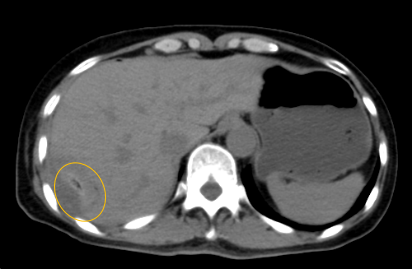

入院后,影像診療中心立即給李女士完善了CT和MR檢查,發(fā)現(xiàn)病變位于肝包膜下,臨近膈肌,消融治療過(guò)程中有并發(fā)損傷膈肌的可能,難度較大,但是采用精準(zhǔn)影像定位是可以完成的。陳寶瑩主任立即與腫瘤三病區(qū)劉金鵬主任聯(lián)系,并與影像微創(chuàng)治療小組進(jìn)行MDT討論:患者為卵巢癌肝右葉包膜下單發(fā)轉(zhuǎn)移瘤,最長(zhǎng)徑不超過(guò)3cm,患者對(duì)局部治療的主觀愿望強(qiáng)烈,符合消融治療專(zhuān)家共識(shí),遂制定了影像引導(dǎo)下局部消融治療聯(lián)合全身治療的綜合治療方案。

針對(duì)這個(gè)特殊部位的腫瘤,要想消融完全,那么膈肌損傷的風(fēng)險(xiǎn)就很高,陳寶瑩主任帶領(lǐng)影像微創(chuàng)亞專(zhuān)業(yè)組成員仔細(xì)閱讀CT圖像,設(shè)計(jì)進(jìn)針路徑,結(jié)合MR圖像確定腫瘤活性范圍,制定了周密而詳盡的消融計(jì)劃。臘月二十九,即住院第二天影像微創(chuàng)治療小組圓滿(mǎn)為患者完成了腫瘤微波消融治療,觀察24小時(shí)后出院回家過(guò)年。術(shù)后48小時(shí)隨訪患者無(wú)明顯不適,術(shù)后7天隨訪,患者肝功、血常規(guī)等各項(xiàng)指標(biāo)均恢復(fù)正常。